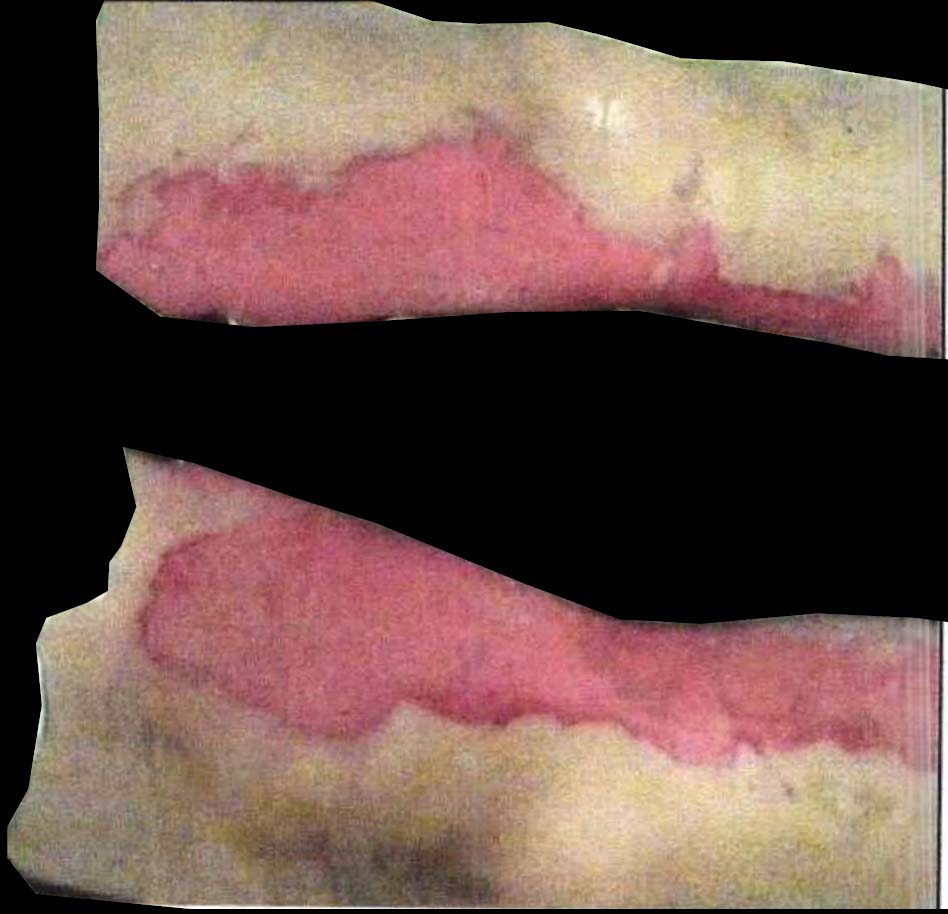

Figure 2a. illustrates the information retrieved from this CNN model from various layers of the architecture that is used to create a BAM map, which is used to segment the burn injury from normal skin in a 2D image. First, the heatmaps for the activations of the first convolutional layer are computed (Figure 2a(ii)), and then Grad-CAM heatmap is computed using the last convolutional layer (Figure 2a(iii)). Once the first convolutional layer heatmaps and Grad-CAM are generated, the algorithm uses a three-round iterative process to select activation heatmaps that have the highest correlation to the Grad-CAM heatmap among the channels of the first layer activations. After the process of correlating and selecting heatmaps is completed (Figure 3 ), segmentation masks are created next (Figure 4). A final composite BAM mask is created as illustrated in 2b(i). Finally, figure 2b (ii-iii) illustrates how the BAM mask is superimposed on the input image to segment the burn injury area, and how edge detection may be applied to the BAM mask in order to obtain a fine-tuned segmented boundary superimposed on the input image.

Once the heatmaps with the highest correlation coefficients are selected, these high-resolution visualizations are utilized as the input to make binary segmentation masks as illustrated in Figure 4(i). The generation of masks uses Gaussian components of the maps to find thresholds (Figure 4(ii)) and subsequently uses the highest Intersection-Over-Union (IOU) values (Figure 4(iii)) between the binary masks generated and the Grad-CAM to select the final mask. The generated binary segmentation mask lastly undergoes a post-processing step in order to filter out the noise/false positive regions and produce the final BAM mask (Figure 4(iv)), which can be used for super-positioning on the input image (Figure 2b).

Figure 5 shows several burn image examples of patients with different sized burns in different body locations, for which the Grad-CAM heatmap, BAM heatmap, BAM masks, and final superimposed images were created. These results allow us to understand the clinical accuracy of burn segmentation from 2D images using BAM. These images show various degrees of burn. It is evident from the results that given skin burn images and the corresponding Grad-CAM heatmaps highlighting the burn regions even partially, the BAM heatmap is able to highlight the burn regions and display a high resolution heatmap accurately. This is the main contribution of BAM. It can be seen from the figure that the BAM heatmaps display different contrast levels in highlighting the burn regions. More precisely, the more superficial burns are highlighted with a lower contrast to the normal skin. The deeper burns, on the other hand, are highlighted with a higher contrast to the normal skin. Nevertheless, the contrast between the burn regions and the normal skin in the BAM heatmaps is sufficient for generating the binary segmentation masks even for the more superficial burns. As evidenced, the BAM heatmaps can successfully be converted into accurate binary segmentation masks. The rightmost column of the figure shows the BAM segmentation masks on top of the input images in order to better visualize the effectiveness of BAM in segmenting the burn regions. In short, comparing the Grad-CAM heatmaps against the BAM heatmaps and BAM segmentation masks provides evidence for a significant improvement in generating heatmaps that are both class-discriminative and fine-grained.